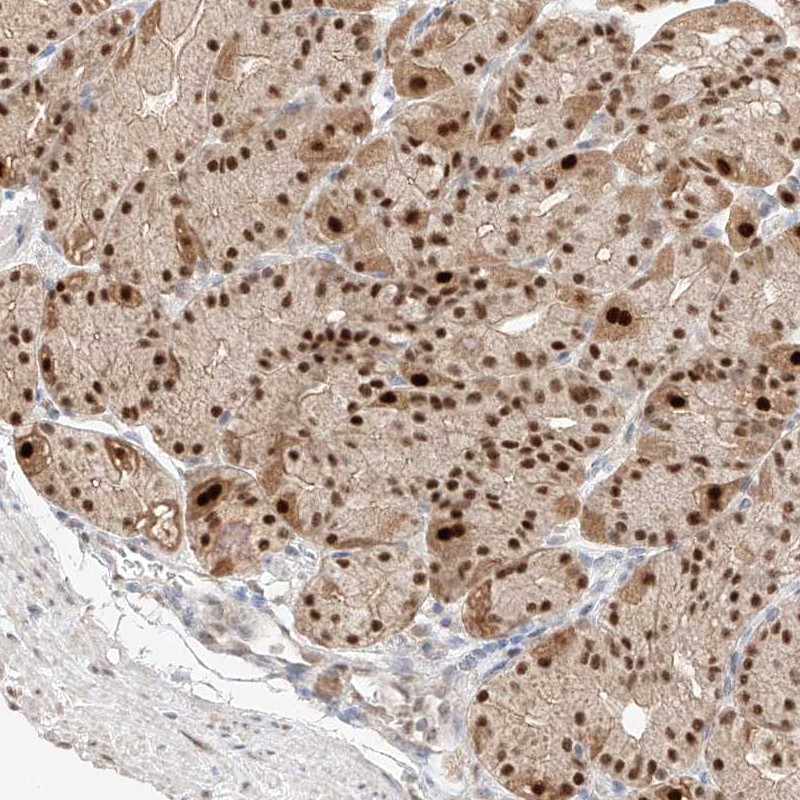

Immunohistochemical staining of human stomach shows strong nuclear positivity in glandular cells.